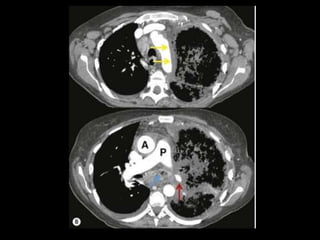

TC: o aspecto típico é de uma massa regular,

lobulada, redonda ou oval, ou até o de uma

formação serpenginosa, com menos de 1 cm a

vários cm de tamanho, associada a uma artéria

nutriz visivelmente aumentada e uma veia de

drenagem alargada;

Uma ANGIO-TC geralmente faz o diagnóstico;

Tratamento pode ser realizado com terapia

embólica.

MAV complexa